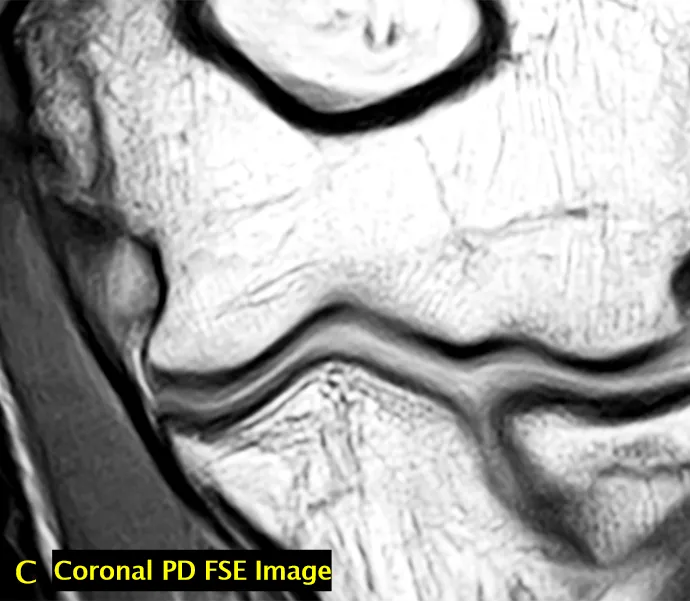

• 完整的内侧副韧带前束(AMCL)复合体(C 图):其远端附着点可位于关节线下 3mm 处(箭头标注);成像序列:冠状面 PD 加权图像。